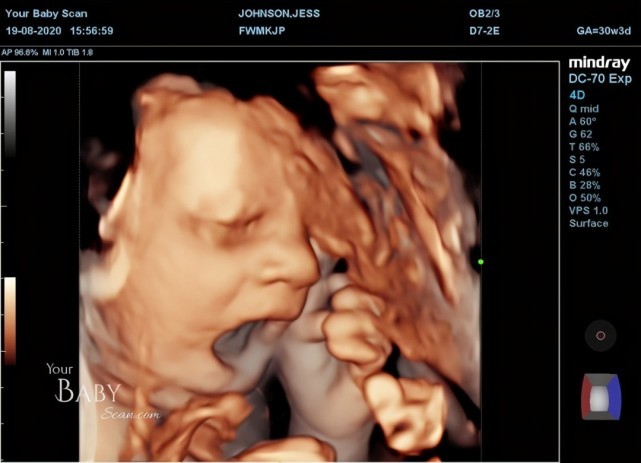

【胎兒動作】英孕婦做超聲波產檢驚見寶寶「舉中指」 媽媽:等他出生我一定提起這件事取笑他!

據外媒報導,由於新冠疫情肆虐,在防疫限制令下,24歲孕婦杰絲(Jess Johnson)預約不到醫院做產檢。約30周身孕時,她到私人機構照超聲波,查看寶寶的狀況。

在產檢的過程中,23歲未婚夫大衛(David Lewis)和杰絲一起細心觀察寶寶動態,並形容兒子開頭有些害羞地把臉遮起來,有時還做出類似「打喊露」的動作,在結束產檢5分鐘前,他們發現兒子做出不雅的手勢:「他對我們舉中指,就好像在說『看夠照片了,別打擾我』。」杰絲表示,舉中指動作沒有維持太久,但認為BB十分搞怪。「等到他出生,我一定會提起這件事取笑他。」